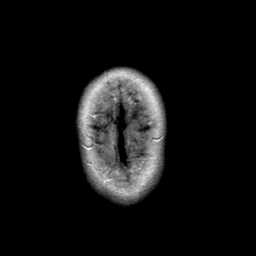

Stroke: proton density-weighted MR #1 -- Slice #23

[Home][Help][Clinical] Slice 23